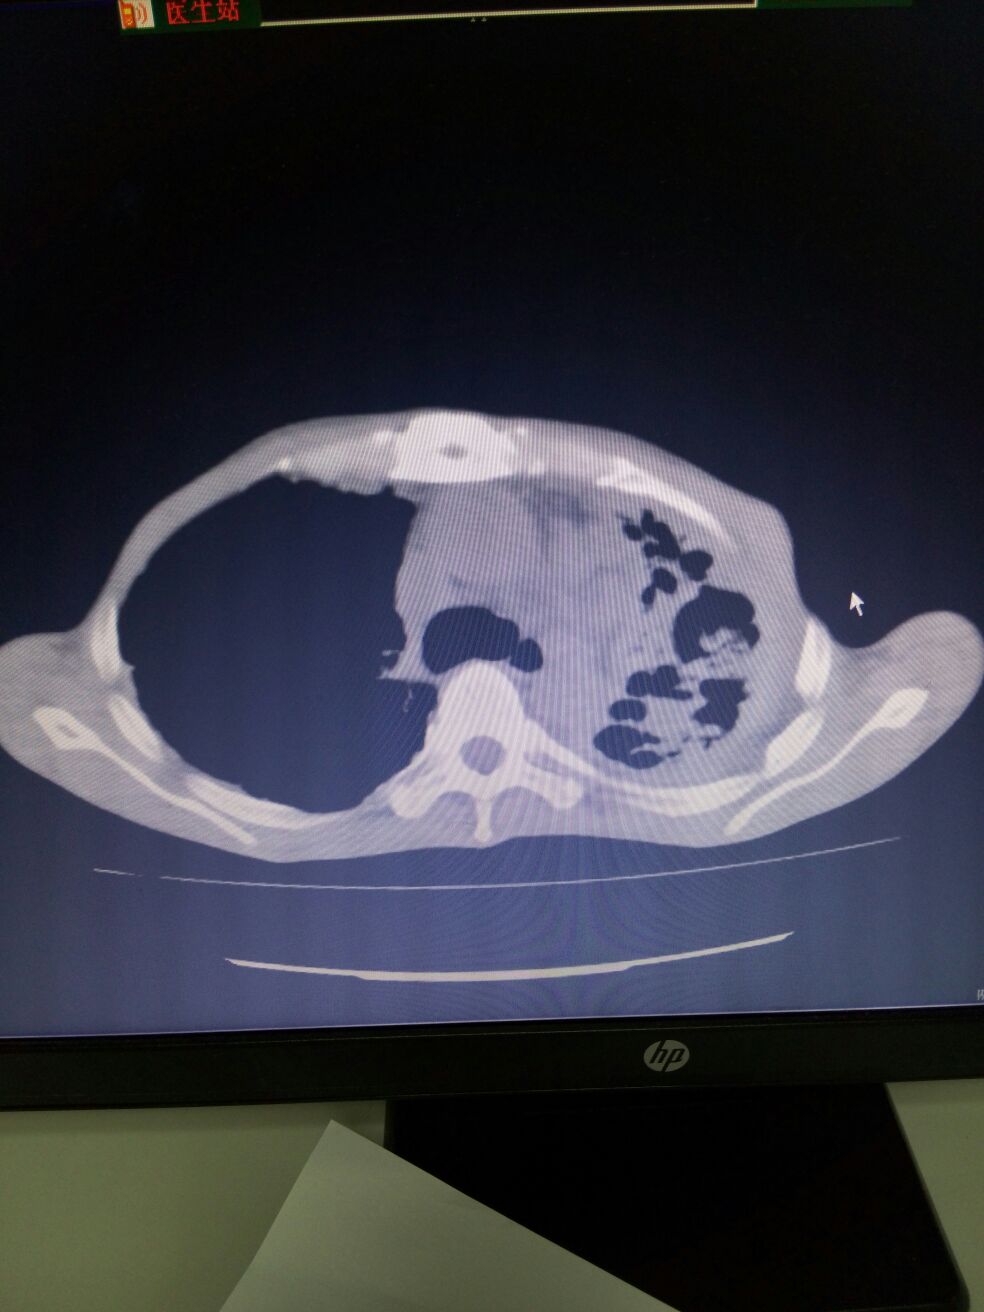

1.左上肺体积缩小,呈多囊状改变,不除外左肺发育不良并感染可能。2.双肺散在感染。3.右上肺多发肺大疱。4.两侧胸膜增厚,左侧伴钙化。5.纵膈多发增大淋巴结。